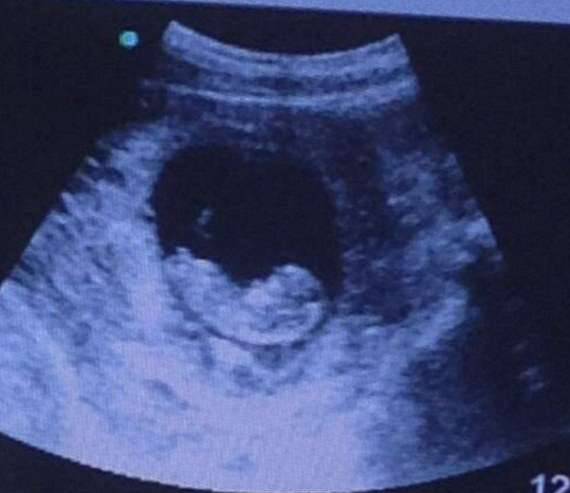

準妈妈们怀孕后都会定期到医院检查,时刻关注宝宝的健康状况。下面这名準妈妈去医院照超音波,胎儿看起来很健康,但一旁的阴影中却有一个模糊的可怕影子。朋友将这张照片上传到网路上,立刻引起网友们的讨论。

▼从照片中可以看出,胎儿睡得很安稳,但右侧的阴影处却好像有个恶魔?!

就在大家都争论不休时,网友解释说:「宝宝非常健康,现在準妈妈刚刚怀孕2个月。亲友看到照片后也询问了医生,但没有得到确切的答案,因为这样的事情之前并没有发生过。」